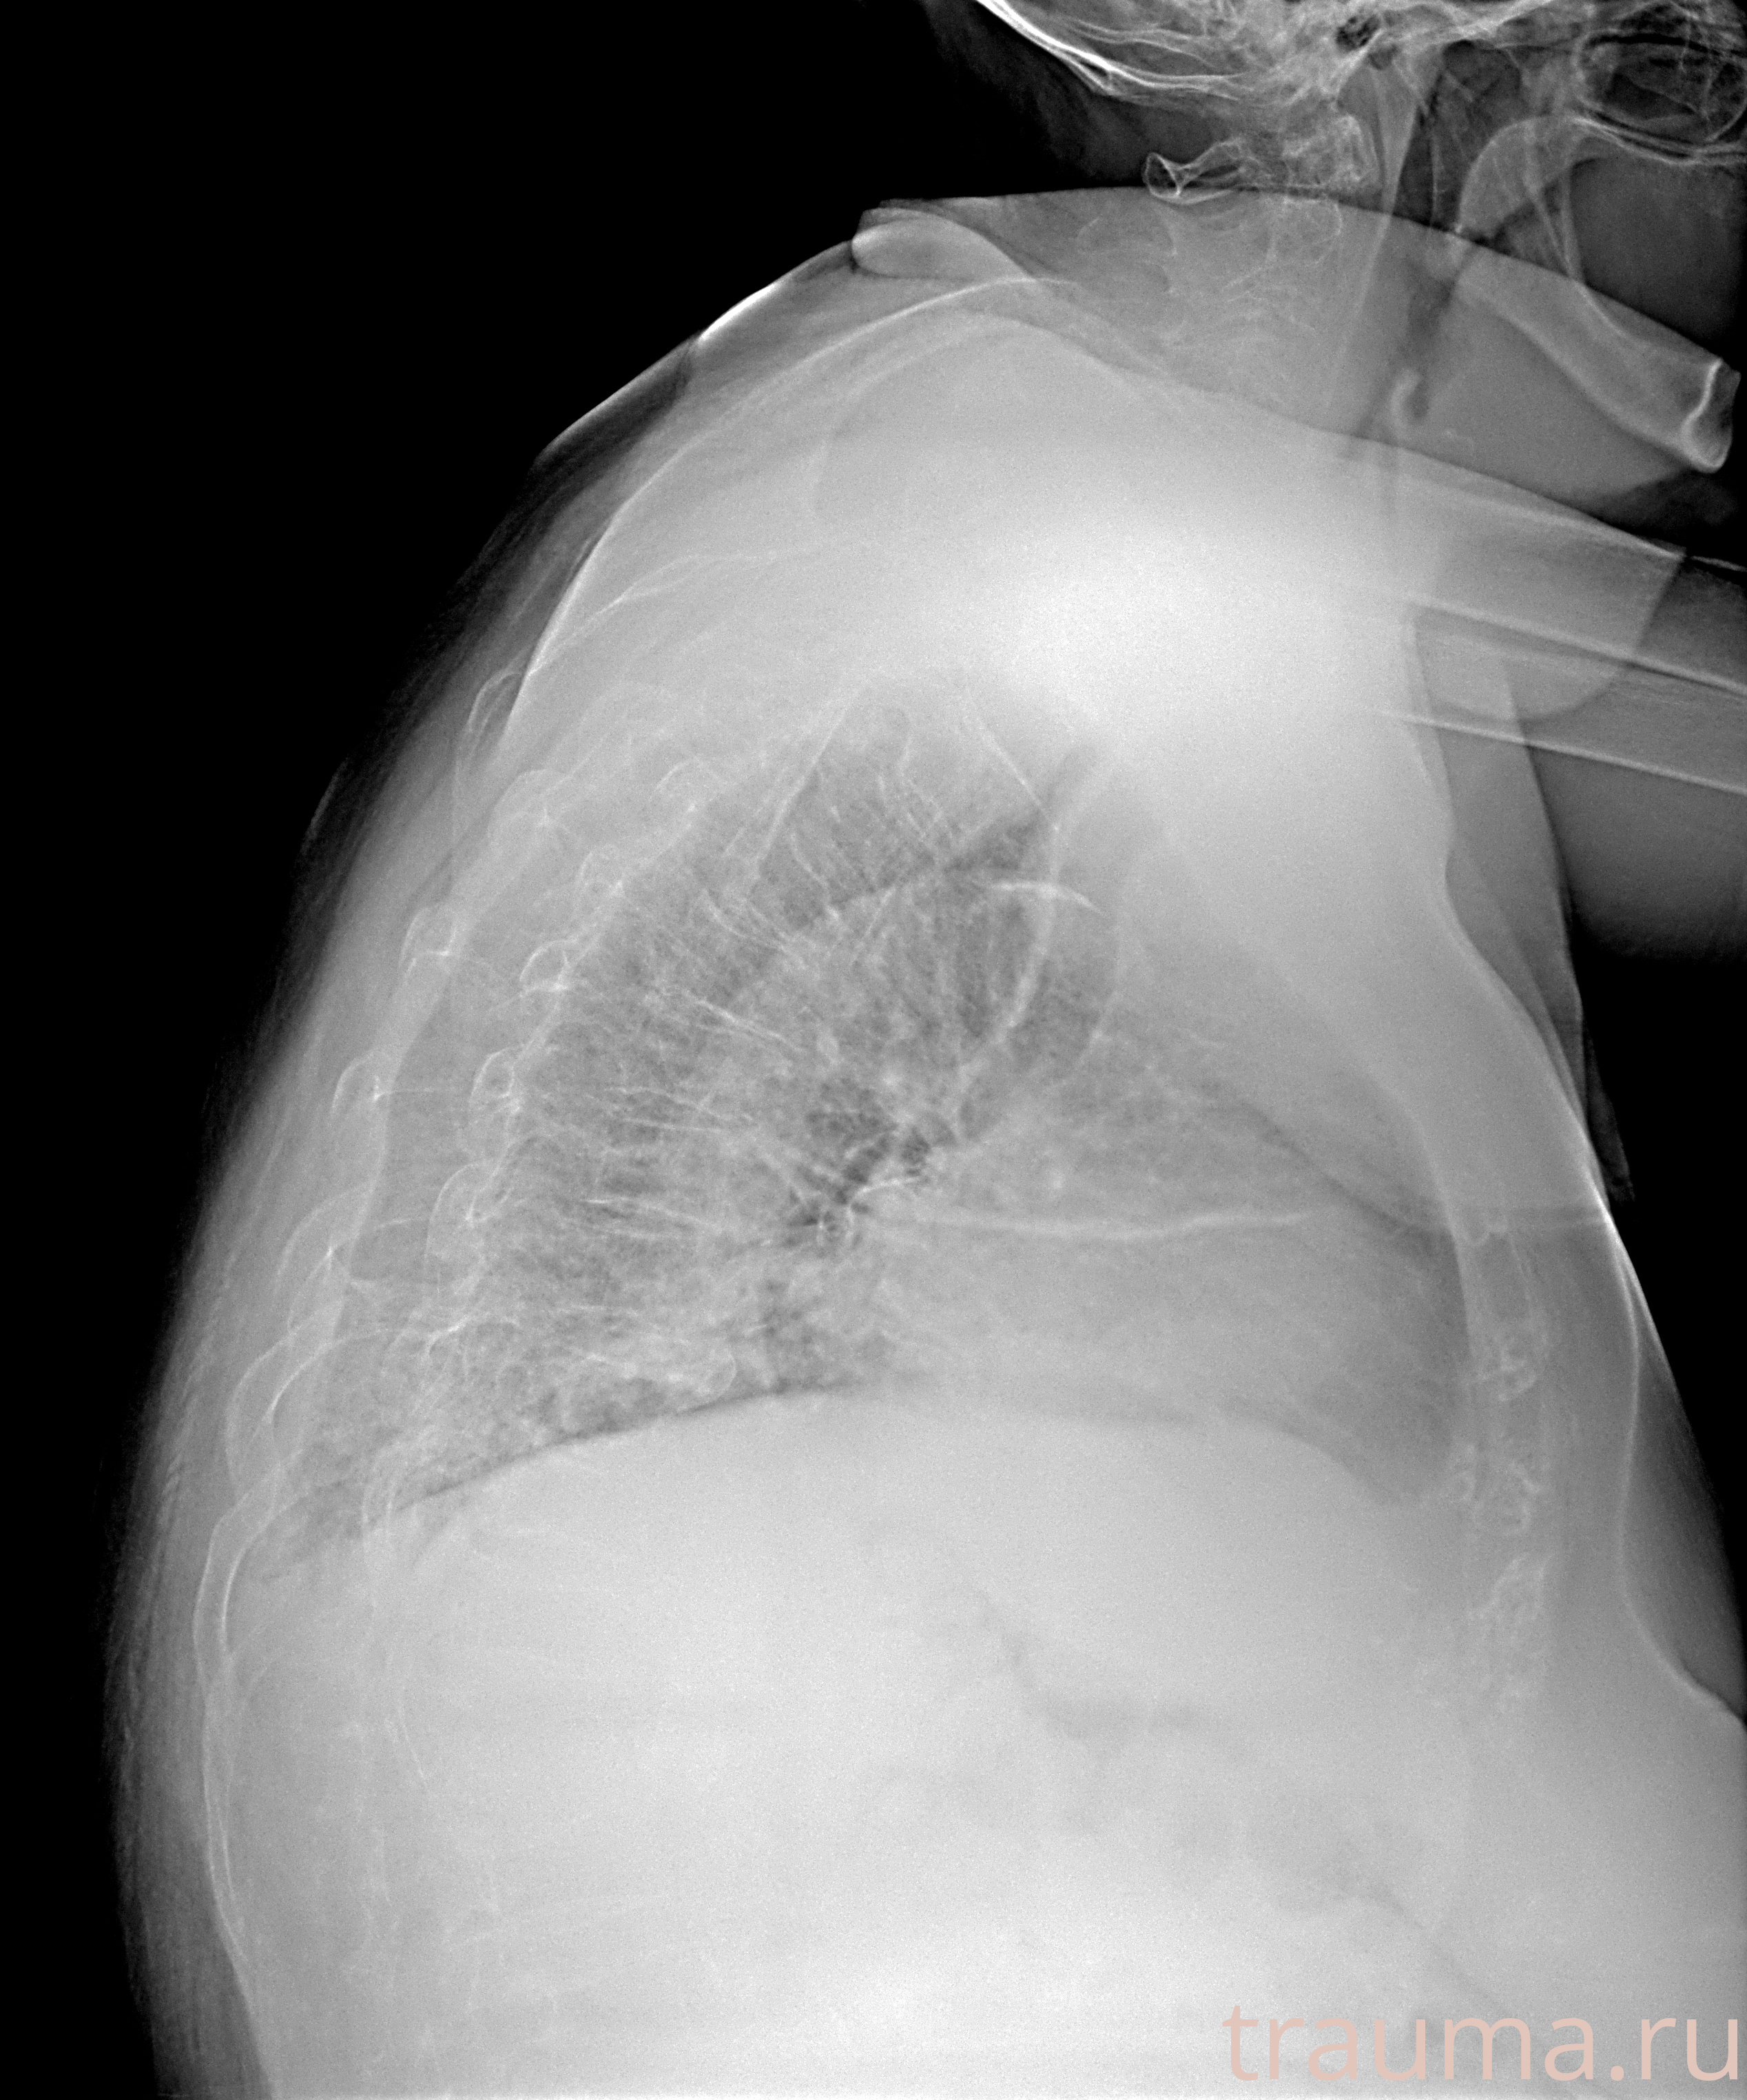

Перелом 3-5 ребер слева

Рентген на дому: по вашему адресу приезжает врач-рентгенолог, травматолог-ортопед с мобильным рентгеновским аппаратом, проводит диагностику травмы или заболевания, делает необходимые рентгенограммы, дает рекомендации по дальнейшему лечению. Получить качественные снимки в домашних условиях возможно благодаря уникальной методике, разработанной МосРентген Центром для института  Склифосовского